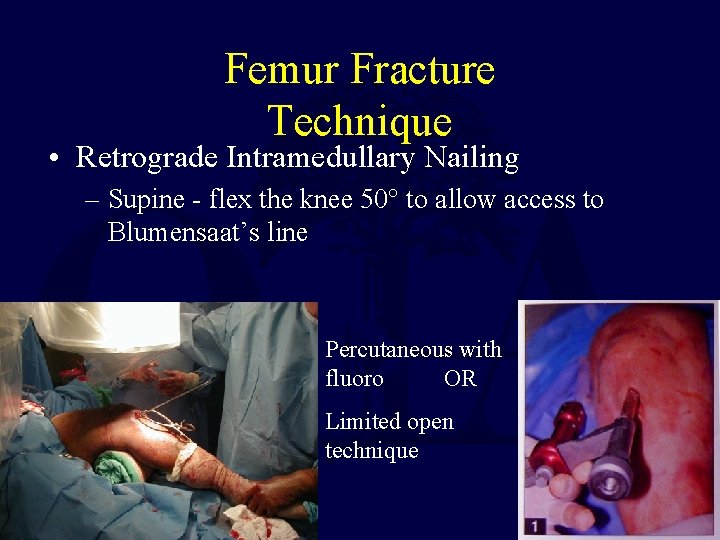

Femur Fracture Technique • Retrograde Intramedullary Nailing – Supine - flex the knee 50° to allow access to Blumensaat’s line Percutaneous with fluoro OR Limited open technique